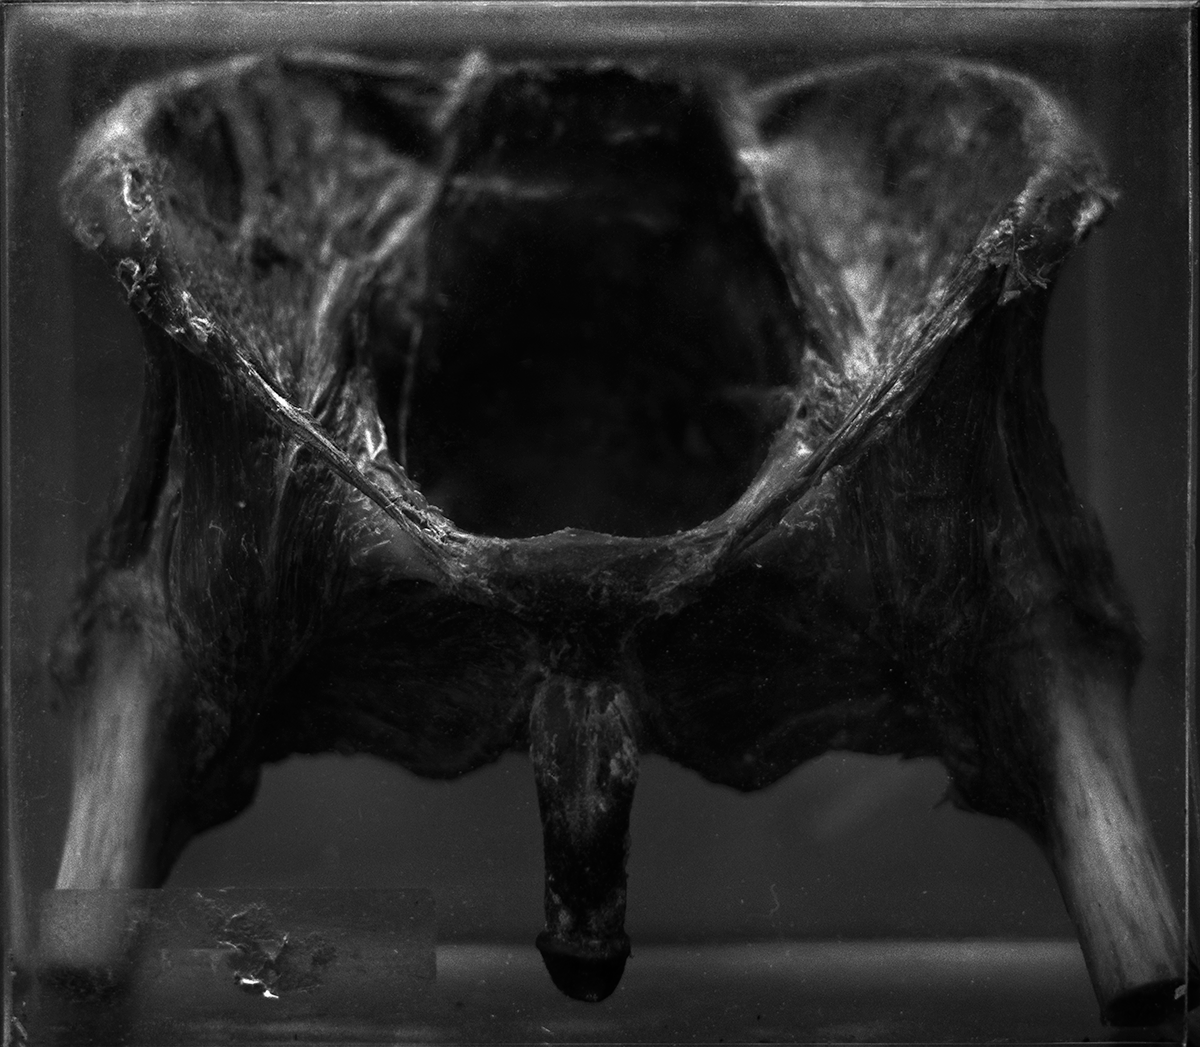

The OJardim series was created using a fictional storyteller that Daniel Malva imagined. The images have names which refer toarche types created by humanity to tell our story. The series has 25 images of human body parts dried or in formaldehyde solution. They were photographed at a collection of anatomy from São Paulo. This work was exhibited in São Paulo in 2015 and the works are in the process of being acquired by the City Museum of São Paulo.

The OJardim series was made using a large-format camera (5×7 inches) and medium format (6×7 cm) and a fifth lens built by Daniel Malva. This lens uses the glass’s elements at a better quality compared to other lenses that Malva has built. The result is the ability to show more details of the human anatomy in his pieces.